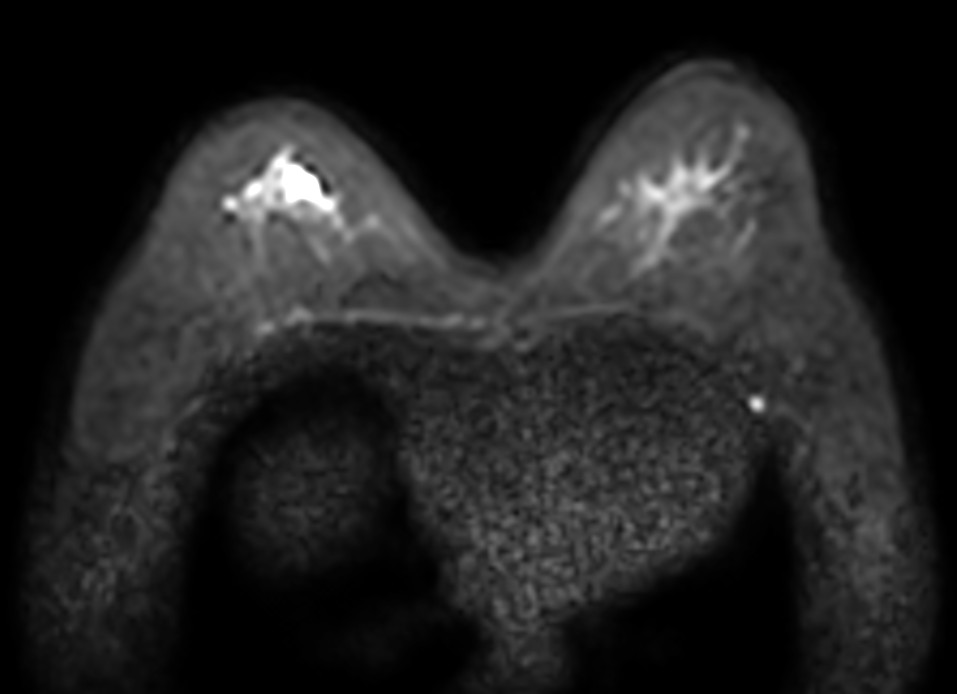

Axial DWIBS b1000